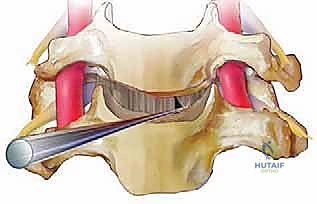

الخطوة 2: الشق الجراحي الأمامي (The Anterior Approach)

لماذا "أمامي"؟ الوصول إلى العمود الفقري من أمام الرقبة (عادة عبر شق أفقي صغير يتراوح بين 3 إلى 5 سم في أحد ثنيات الجلد الطبيعية) يسمح للجراح بالوصول إلى الأقراص الفقرية دون الحاجة إلى قطع عضلات الرقبة الخلفية القوية أو إزعاج الحبل الشوكي بشكل مباشر. يقوم الجراح بإزاحة القصبة الهوائية والمريء والأوعية الدموية بلطف للوصول إلى العمود الفقري.

الخطوة 4: استئصال القرص الغضروفي (Discectomy)

باستخدام أدوات ميكروسكوبية دقيقة، يتم تفريغ وإزالة القرص الغضروفي التالف بالكامل. يتم كشط الغضروف حتى الوصول إلى السطح العظمي للفقرتين العلوية والسفلية.

الخطوة 5: تخفيف الضغط العصبي (Decompression)

هذه هي المرحلة الأهم والأكثر حساسية. يقوم الجراح بإزالة أي نتوءات عظمية (Osteophytes) أو أجزاء من الغضروف الممزق التي تضغط على الأعصاب الشوكية أو الحبل الشوكي، مما يعيد للقناة الشوكية اتساعها الطبيعي.